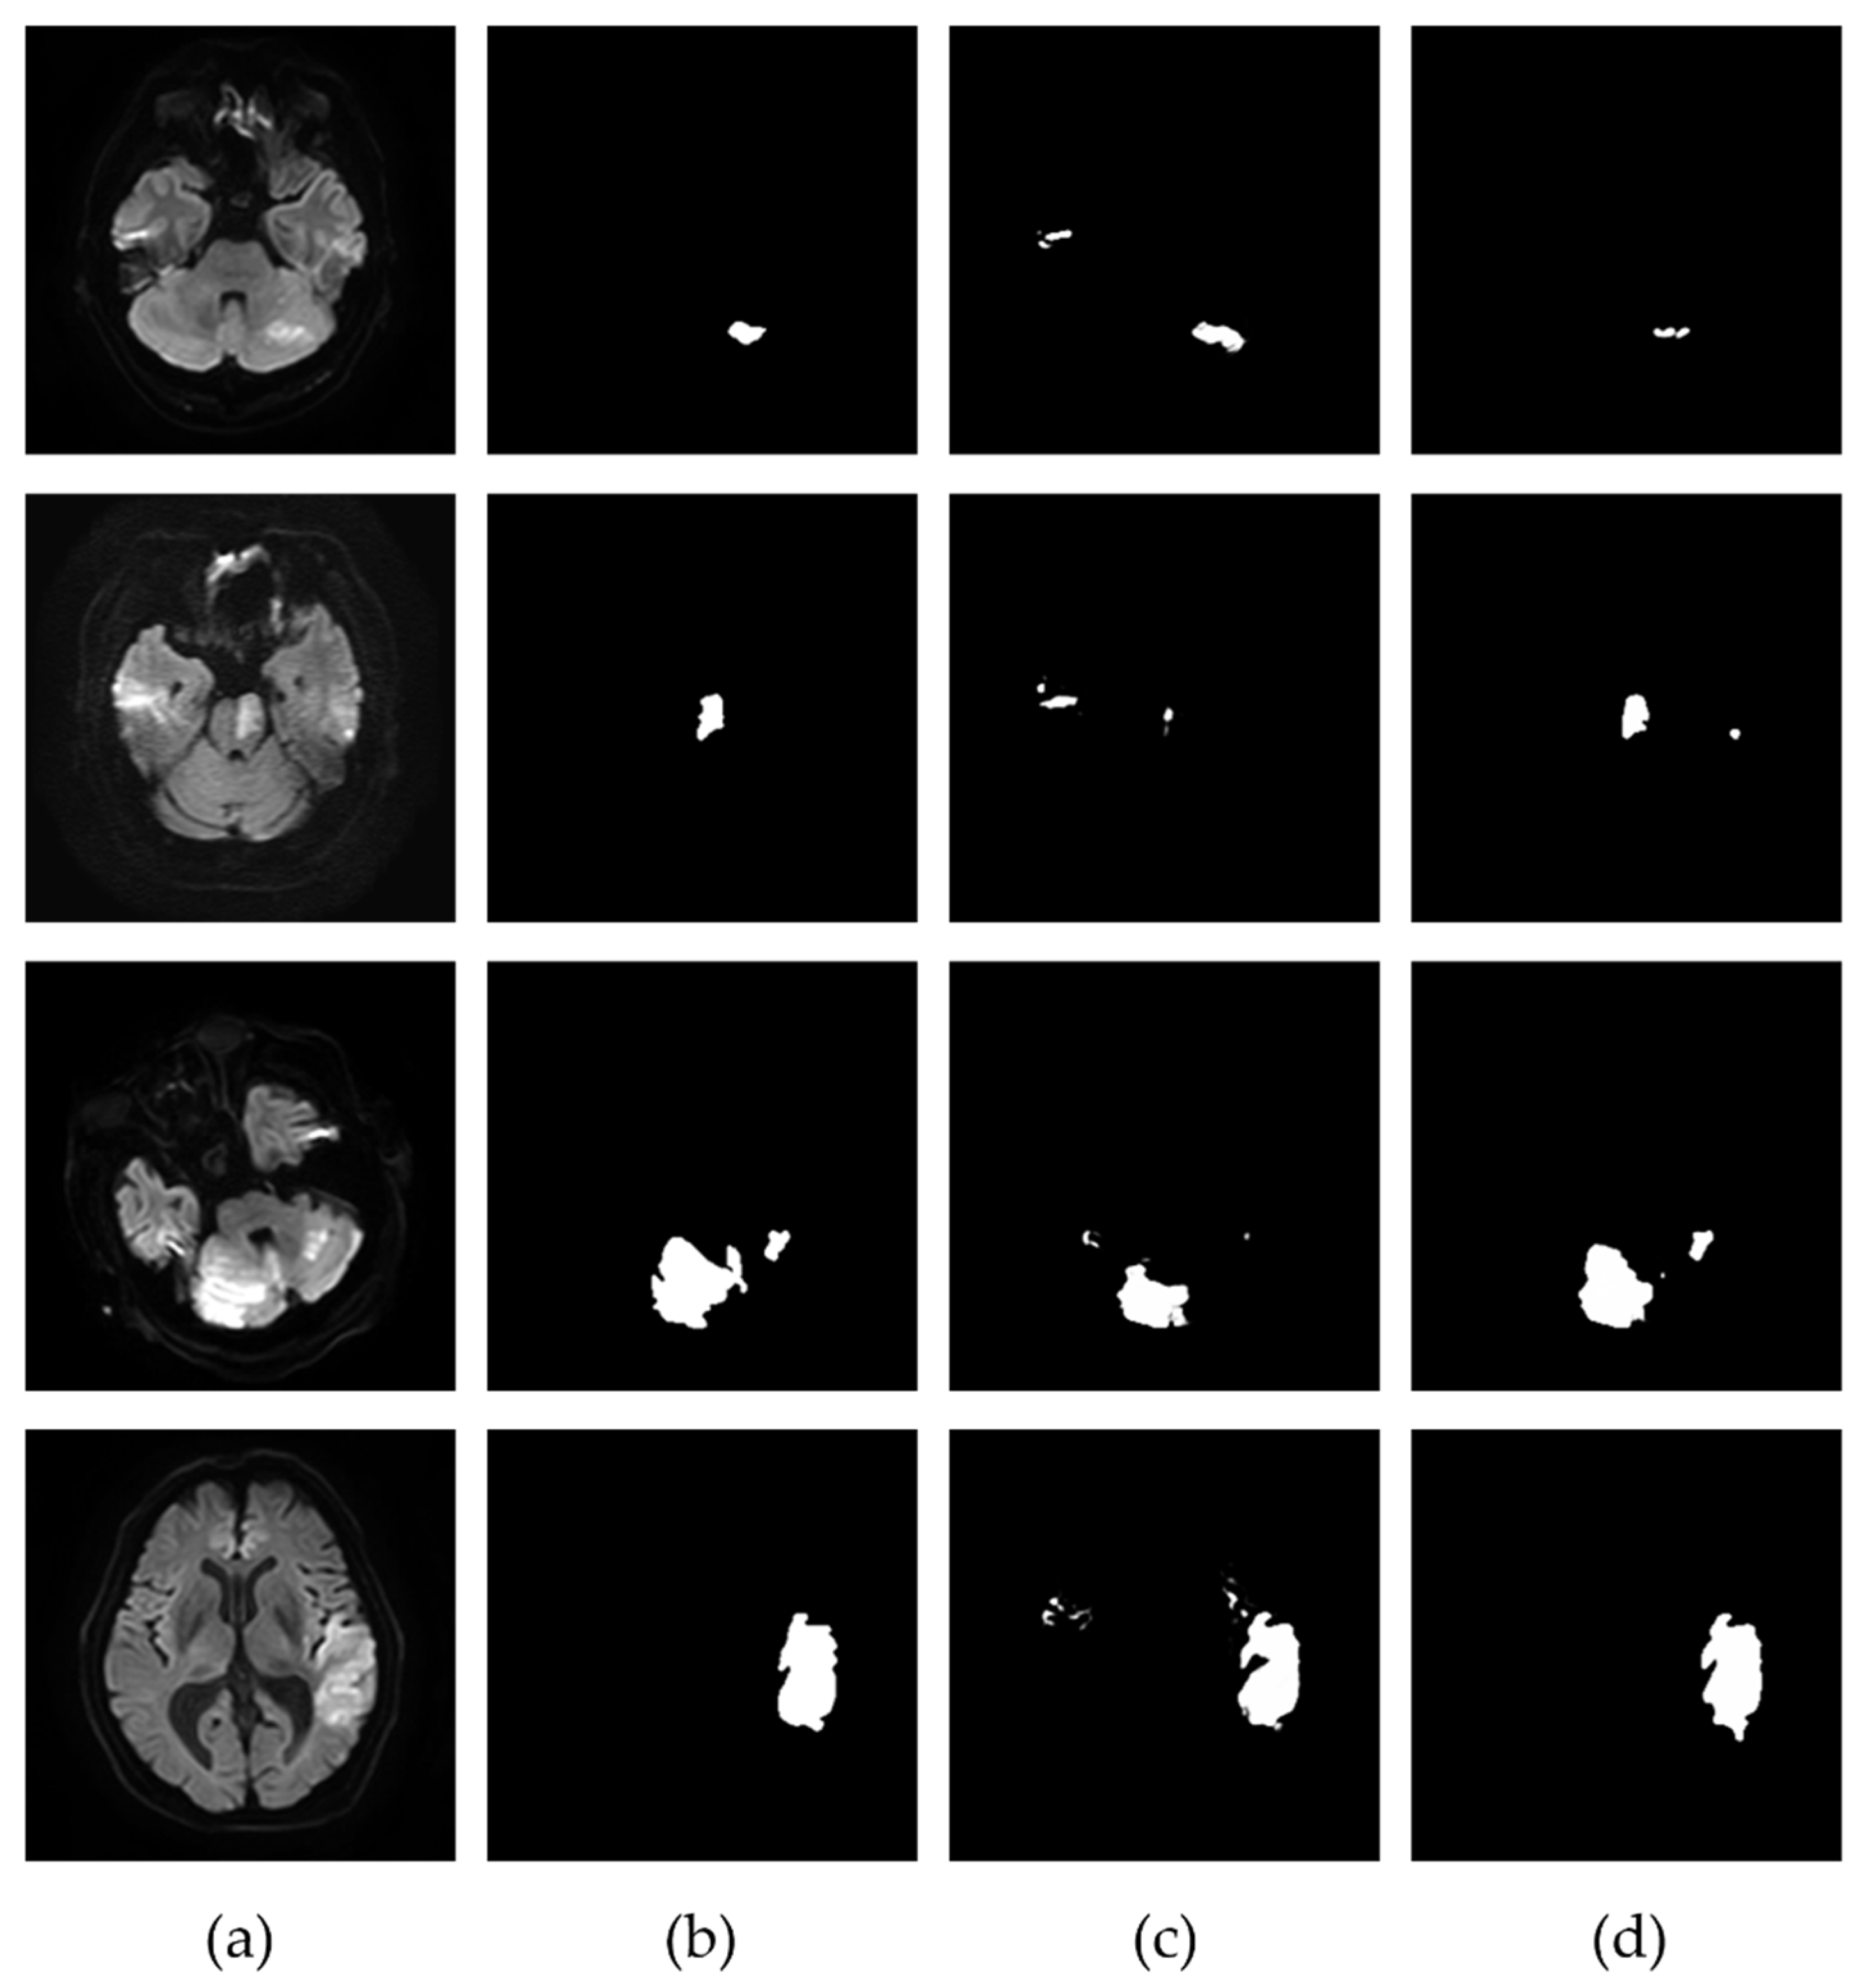

3.2. Extraction of the Infarcted Regions